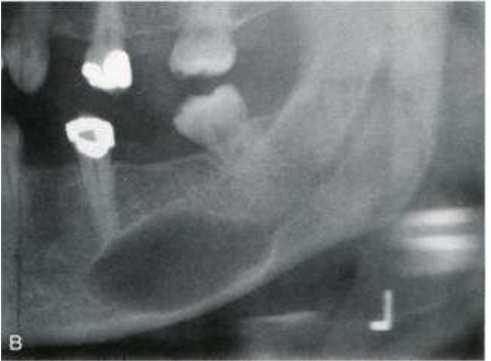

79.承上題,此患者X光片病灶特徵之描述,下列何者錯誤?

(A)病灶的X光分類屬於radiolucent and radiopaque mixed lesion (B)病灶位於左下顎後牙及上升枝,如網球拍狀(tennis racket-like)影像 (C)左下顎第二大臼齒被移位 (D)病灶區的 external oblique ridge及下顎骨板(cortical border)變薄,且上下擴張